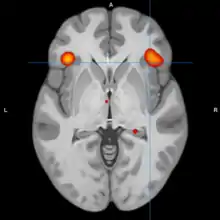

A model of functional neuroanatomy produced by a workgroup led by Stephen M. Strakowski concluded that bipolar was characterized by reduced connectivity, due to abnormal pruning or development, in the prefrontal-striatal-pallidal-thalamic-limbic network leading to dysregulated emotional responses. This model was supported by a number of common neuroimaging findings. Dysregulation of limbic structures is evinced by the fact that hyperactivity in the amygdala in response to facial stimuli has been consistently reported in mania.[33] While amygdala hyperactivity is not a uniform finding, a number of methodological challenges could explain discrepancies. As most studies utilize fMRI to measure blood-oxygen-level dependent signal, excess baseline activity could result in null findings due to subtraction analysis. Furthermore, heterogenous study design could mask consistent hyperactivity to specific stimuli. Regardless of directionality of amygdala abnormalities, as the amygdala plays a central role in emotional systems, these findings support dysfunctional emotional circuits in bipolar. A general reduction in ventrolateral prefrontal cortex activity is observed in bipolar, and is lateralized with regard to mood (i.e., left-depression, right-mania), and may underlie amygdala abnormalities. The dorsal ACC is commonly under-activated in bipolar, and is generally implicated in cognitive functions, while the ventral ACC is hyperactive and implicated in emotional functions. Combined, these abnormalities support the prefrontal-striatal-pallidial-thalamic limbic network underlying dysfunction in emotional regulation in bipolar disorder.[34] Strakowski, along with DelBello and Adler have put forward a model of "anterior limbic" dysfunction in bipolar disorder in a number of papers.[35][36][37][38][39]

During cognitive or emotional tasks, functional neuroimaging studies, consistently find hyperactivation of the basal ganglia, amygdala, and thalamus. Prefrontal abnormalities are less consistently reported, although hyperactivation in the ventral prefrontal cortex is a fairly consistent finding.[72] Hyperactivity in the amygdala and hypoactivity in the medial and ventral prefrontal cortex during exposure to emotional stimuli has been interpreted as reflecting dysfunction in emotional regulation circuits. Increased effective connectivity between the amygdala and orbitofrontal cortex, and elevated striatal responsiveness during reward tasks have been interpreted as hyper-responsiveness in positive emotion and reward circuitry. The abnormal activity in these circuits has been observed in non-emotional tasks, and is congruent with changes in grey and white matter in these circuits.[73] Neural response during reward tasks differentiates unipolar depression from bipolar depression, with the former being associated with reduced neural response and the latter being associated with elevated neural response.[74] An ALE meta analysis of functional neuroimaging comparing adults and adolescents found a larger degree of hyperactivity in the inferior frontal gyrus and precuneus, as well as a larger degree of hypoactivity in the anterior cingulate cortex in adolescents relative to adults[75]